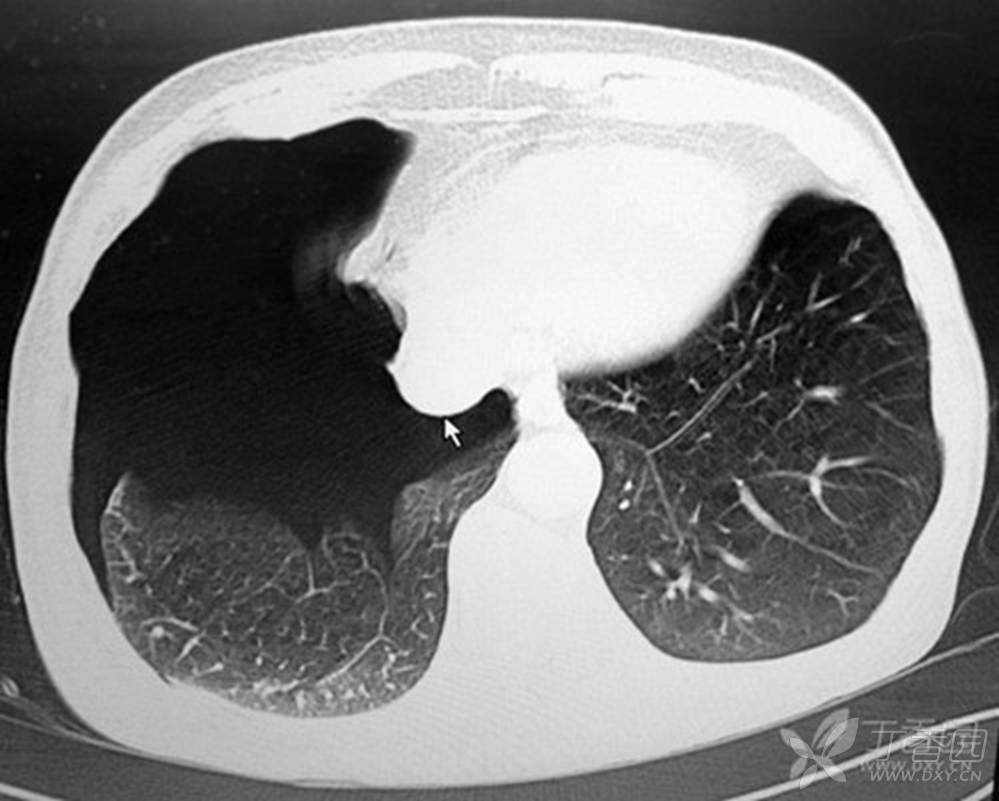

门诊ct检查提示:右侧气胸,肺压缩约70%,右侧肺尖部肺大泡形成.